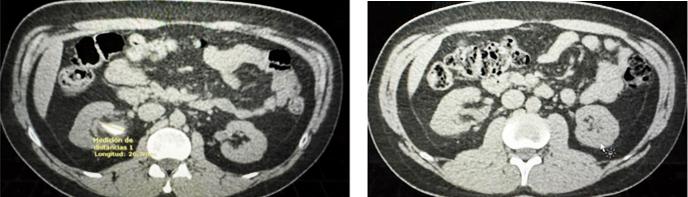

Funding: None

Authors’ contributions: M A A D , W D C M , A M T

Acknowledgments: None

REFERENCES